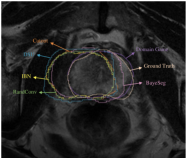

Fig. 2a presents the qualitative segmentation results. Notably, DSU and Domain Game consistently deliver satisfactory outcomes, with Domain Game more resembling the labels. Fig. 2b presents a comprehensive comparative analysis within an example of the UCL domain. The results reveal that all the methods other than Domain Game exhibit a leftward bias, while Domain Game notably preserves a closer alignment to the ground-truth label.

| (a) Visualization for cross-site prostate segmentation. | (b) Detailed comparison. |